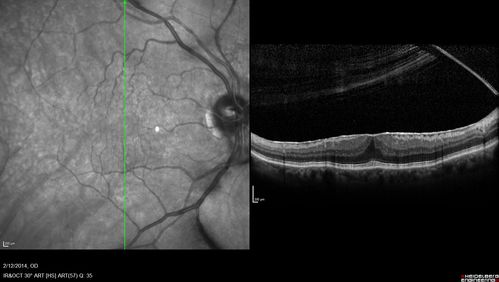

Macular Hole Left Eye - progression from VMT - Stage II macular hole - Spontaneously Closed Macular Hole

Pucker in fellow eye is stable

Macular Hole from Vitreomacular traction to Stage II hole to Spontaneously Closed Hole